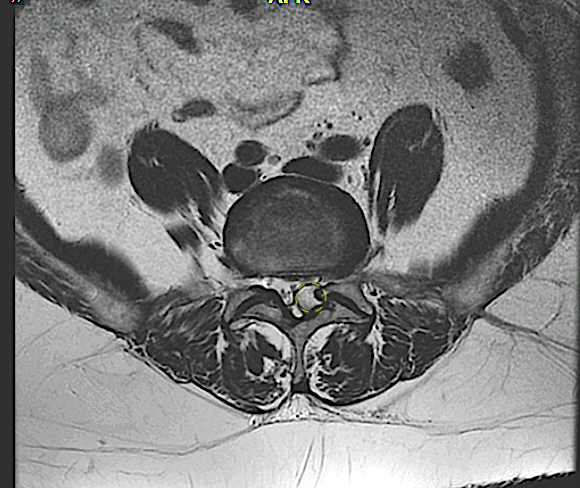

En la figura se aprecia el quiste sinovial (amarillo, discontinuo) que comprime el saco dural y estrecha el receso lateral, guardando relación de proximidad con una faceta. En este caso se eligió un abordaje microscópico con exéresis simple.

protrusion discal con rotura del anillo posterocentral asociado aún quiste sinovial de origen facetario izquierdo heterogéneo de 10 mm